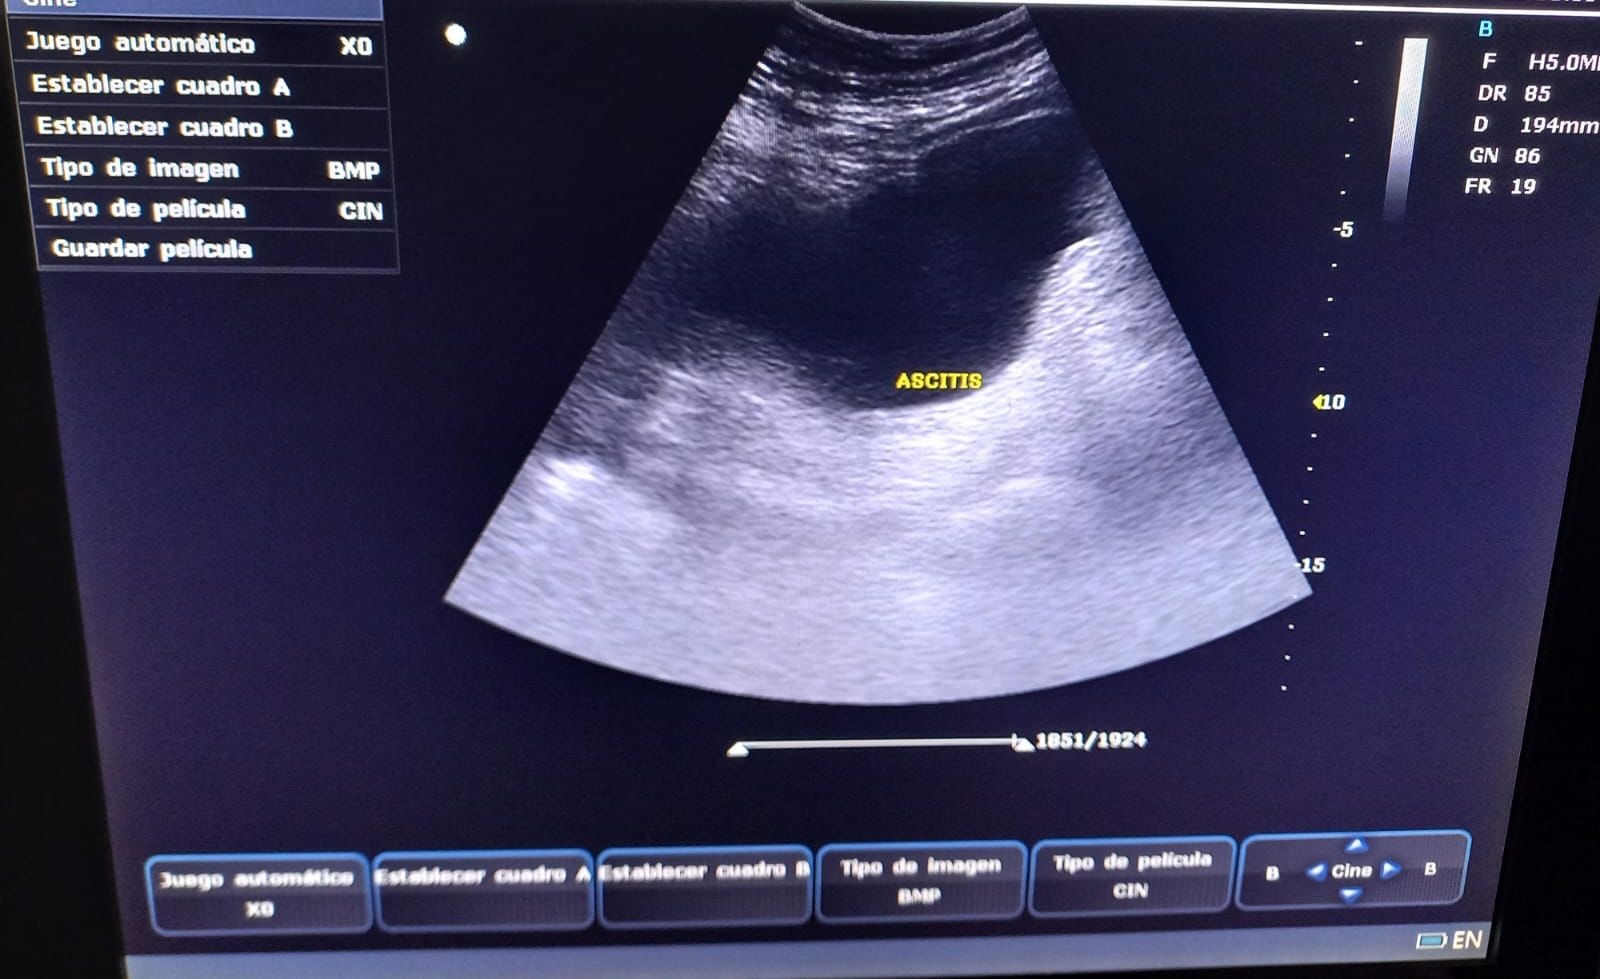

Desde 2022, tras la incorporación de un ecógrafo portátil en nuestro servicio, iniciamos formación específica en ecografía pulmonar, lo que permitió valorar el grado de congestión y la presencia de derrame pleural (DP) en pacientes con insuficiencia cardíaca congestiva (ICC), así como condensaciones pulmonares en casos de neumonía. En 2024, cursamos un Máster en ecografía clínica para atención primaria, incorporando el protocolo VEXUS para evaluar la congestión venosa sistémica. En 2025, completamos dos cursos semipresenciales que consolidaron esta práctica. La ecografía se integró en las visitas domiciliarias, optimizando tratamientos deplectivos y permitiendo seguimiento sin necesidad de traslados hospitalarios. El análisis de su uso entre enero de 2024 y junio de 2025 evidenció su valor clínico y la necesidad de formación específica para el equipo médico de HAD-AI.